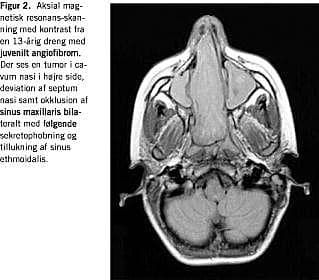

CT skal udføres uden og med kontrast, som koronal og aksial skanning. Denne undersøgelse er især velegnet til at afsløre displacering og udtynding af ossøse strukturer med (Figur 1 ), men MR-skanning er den vigtigste undersøgelse. Ved denne undersøgelse ses, at tumoren udviser kraftig kontrastenhancement efter gadoliniumindgift. MR-skanning skal udføres i tre planer og er især vigtig, når tumorens udgangspunkt og udbredelse skal konstateres (Figur 2 ) [1]. Arteriografi skal udføres som bilateral carotis externa- og interna-arteriografi for at fastlægge tumorens karforsyning. Det er vigtigt, at såvel a. maxillaris interna som a. pharyngea ascendens kan ses, da hovedforsyningen ofte kommer herfra [2].